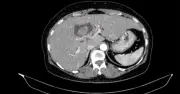

Một phụ nữ 59 tuổi được phát hiện đồng thời ung thư đại tràng và ung thư đường mật trong gan tại Bệnh viện Bạch Mai. Ca phẫu thuật triệt căn thành công nhờ thăm khám toàn diện và hội chẩn đa chuyên khoa.